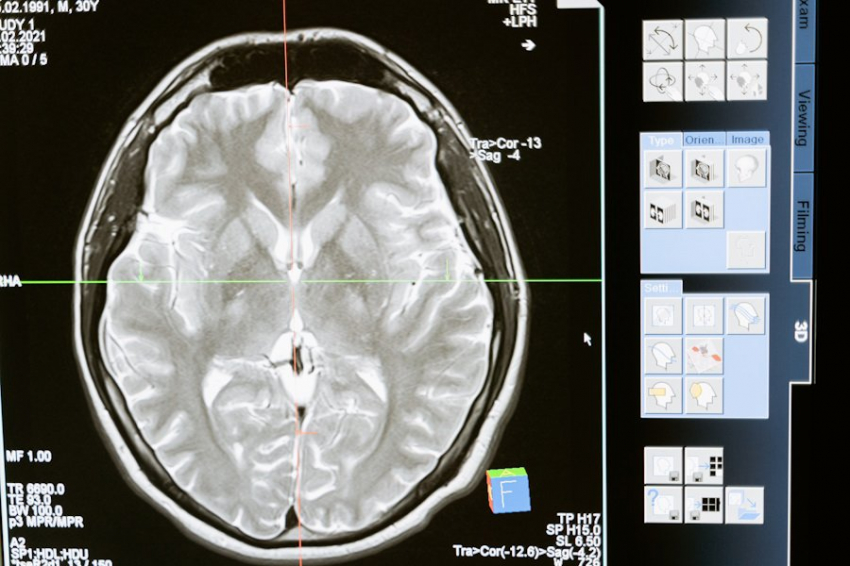

Учёные из University of Tsukuba и University of Tokyo сделали важное открытие в области изучения сна, обнаружив нейронный центр, отвечающий за фазу быстрого сна. Исследование, опубликованное на портале Cell, проливает свет на механизмы, управляющие этой загадочной фазой, когда человек видит сновидения и формируются ключевые когнитивные навыки.

Быстрый сон начинается спустя 60-80 минут после засыпания и сопровождается активной работой мозга. Именно в это время у человека возникают сновидения, а также формируются способности к обучению и творчеству. Учёные исследовали, как нейроны в верхней части ствола мозга, области, называемой мостом, влияют на протекание этой фазы у лабораторных мышей.